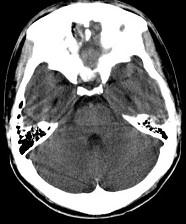

问题 男,23岁,近3天感到头痛、头晕,乏力,精神焦虑,CT检查如图所示,最可能的诊断为()

选项 A.脑萎缩 B.脑室出血 C.正常颅脑 D.脑水肿 E.胶质瘤

答案 C